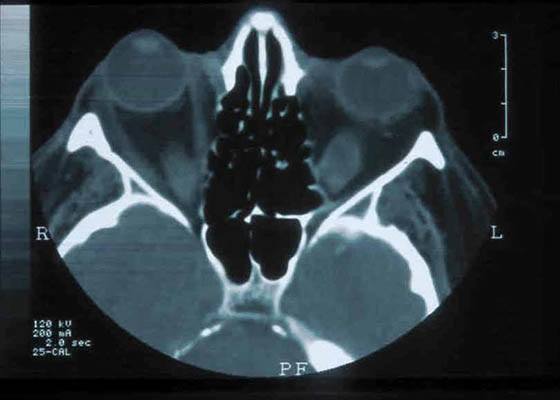

Protruding eyes (exophthalmus) in Graves’ disease

Chronic immune system-mediated inflammation can lead to an increased amount of connective tissue forming behind the eye, which pushes the eyeball forward – and severely limits its mobility. These changes also cause the eye muscles to swell.Please note that orbital decompression in protruding eyes in Graves’ disease can only be treated once the orbit shows no more signs of active disease and is “calm” for 12 months.”

In active endocrine orbitopathy, treatment usually comprised of medical therapy (with certain drugs) and/or surgical treatment of the thyroid. Orbital decompression surgery, to relieve these issues, only becomes an option once the diseases has stopped progressing for a period of at least one year. Orbital decompression surgery involves removes bone from the eye socket so that the swollen eye muscles have more space to reside, and no longer push the eye forward. Clearly, this does not treat the underlying disease, but rather, but it can greatly improve a patient’s quality of life, as it ensures normal eyelid closure and also helps restore the patient’s own self-image: looking in the mirror and seeing a reflection of themselves with bulging eyes can be difficult to bear. There are a number of surgical techniques that can be used to achieve orbital decompression, performed by various specialists, including facial surgeons, ear, nose and throat surgeons and orbital surgeons. The latter are highly specialized eye surgeons who treat all diseases around the bony eye socket. There are several techniques that can be used to perform this surgery – and they differ in both approach and result. Most facial surgeons prefer “transantral” approach, in which the facial skin is released at the top of the skull and “folded” down, so that the eye socket is freely accessible. You can appreciate why we chose not to show illustrations of this approach on the website. Most orbital surgeons, including Dr. Dr. Paridaens, prefer access via the lower eyelid with a ~3 mm-long, hidden, cut. This has the benefit of much easier and faster wound healing, as the incision is far smaller than the transantral approach. Below are illustrations (© Dr. Dr. Paridaens) that show the different stages of orbital decompression surgery using his preferred approach via the lower eyelid. Read more…